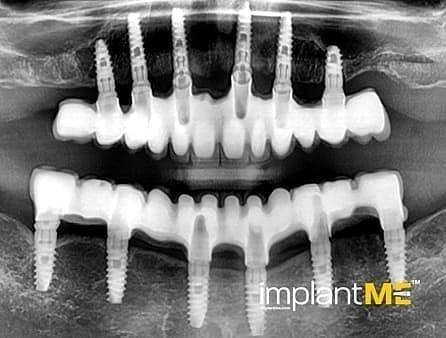

Τα ελκυστικά και ιδιαίτερα υγιή δόντια δεν είναι μόνο καθοριστικό μέρος της εμφάνισής μας, αλλά και της προσωπικότητάς μας. Παλαιότερα, η απώλεια ενός ή περισσοτέρων δοντιών είχε καθοριστικό αντίκτυπο στον τρόπο εμφάνισης των ανθρώπων. Λόγω της σύγχρονης στοματικής εμφυτευματολογίας, αυτό δεν συμβαίνει πλέον. Με συγκριτικά μικρές χειρουργικές επεμβάσεις από το στόμα, μεμονωμένα ή όλα τα ελλείποντα δόντια μπορούν να αντικατασταθούν από εμφυτεύματα, αισθητικά και λειτουργικά ίσα με τα φυσικά δόντια. Μέσω της εισαγωγής εμφυτευμάτων που σχηματίζονται σε ρίζα, είναι δυνατόν να αποφευχθούν αλλοιώσεις των γειτονικών δοντιών και να αγκυρωθούν στεφάνες που δύσκολα διακρίνονται από τα πραγματικά δόντια στα κενά των δοντιών. Οι στεφάνες ή οι γέφυρες που υποστηρίζονται από εμφύτευμα στερεώνονται στα εμφυτεύματα που είναι αγκυροβολημένα στο οστό, γεγονός που δίνει στους ασθενείς μια αίσθηση μάσησης σχεδόν διακριτή από τα δόντια τους. Σε περίπτωση πλήρους έλλειψης δοντιών, τα εμφυτεύματα μπορούν να παρέχουν αξιόπιστες αγκυρώσεις για αφαιρούμενα προσθετικά καθώς και για μεγάλες σταθερές γέφυρες.

Τα οδοντικά προσθετικά που υποστηρίζονται από εμφύτευμα βρίσκονται όσο πιο κοντά μπορείτε να φτάσετε στα φυσικά δόντια. Τα στεφάνια των εμφυτευμάτων βαθμολογούνται με τη φυσική τους εμφάνιση, τα εμφυτεύματα με τη σταθερότητα τους και και τα δύο με τη θετική τους επίδραση στη λειτουργική συντήρηση ολόκληρης της μαστιχικής συσκευής.